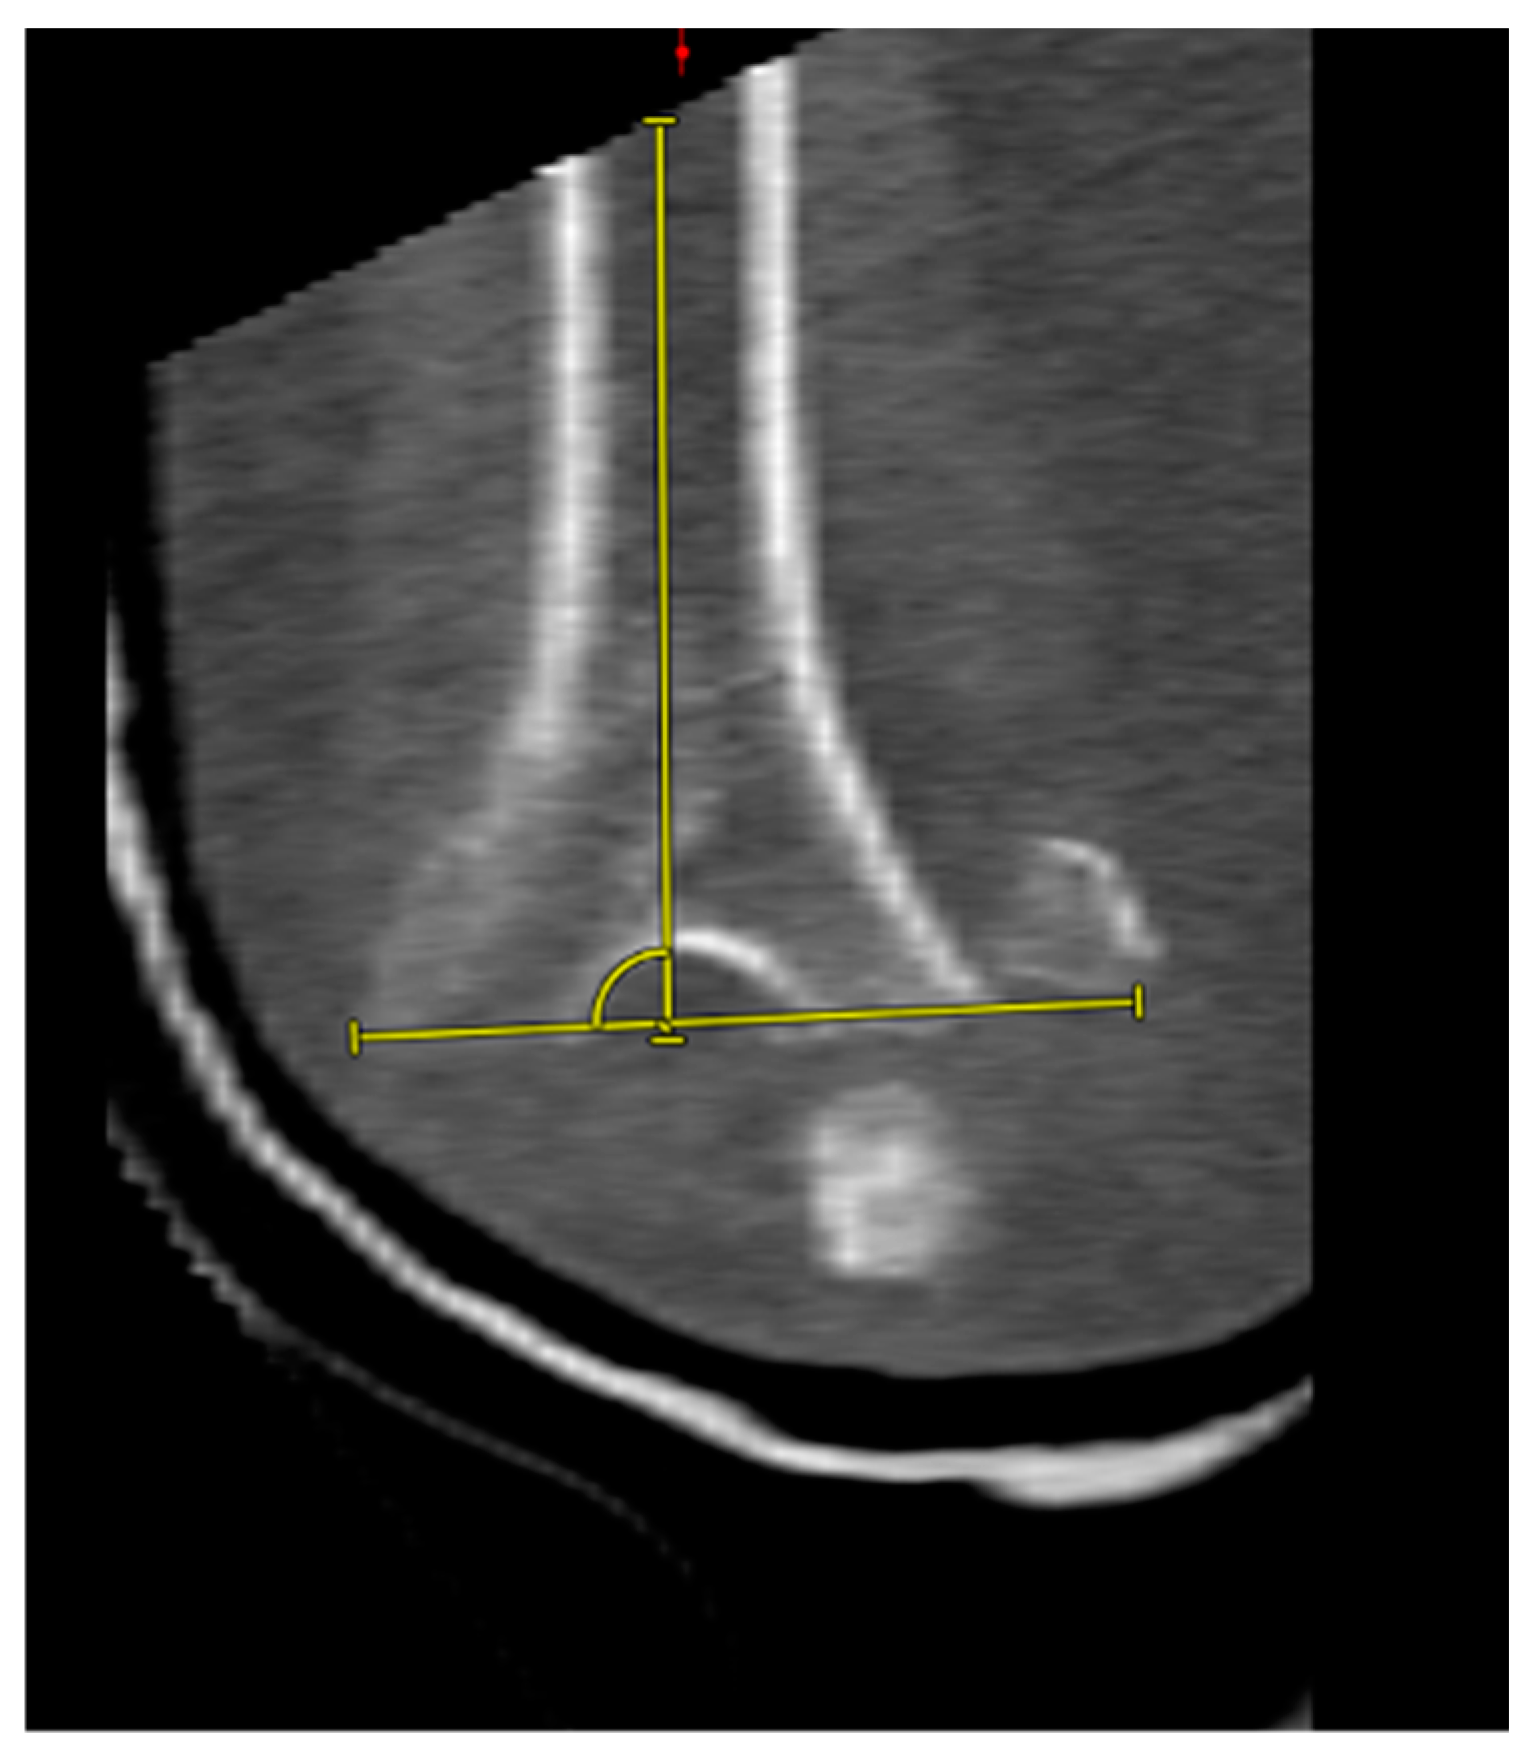

2.4. CT Image Analysis

3.5. Complications